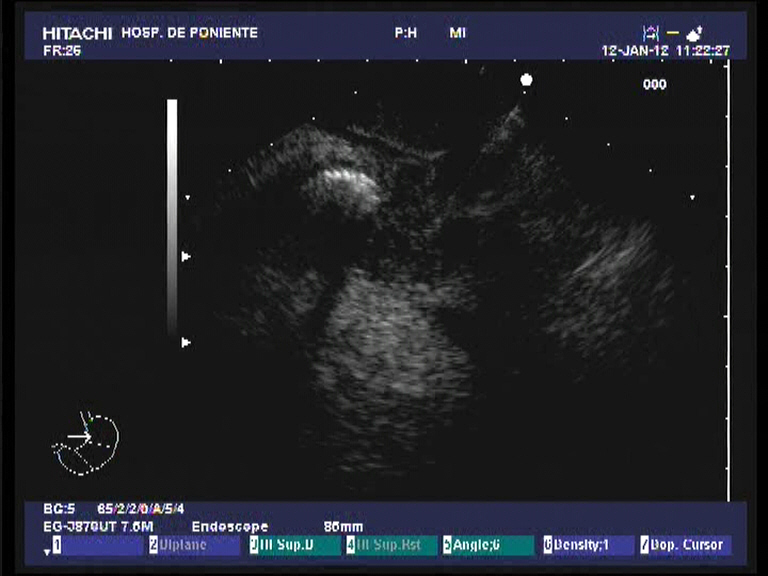

Paciente varón de 60 años de edad, sin antecedentes de interés que presenta dese hace un par de meses pérdida de peso importante (10 kgr), molestias epigástricas vagas junto a coluria e ictericia progresiva. Analíticamente destaca una BRT de 16 mgr/dl, a expensas de la fracción directa (8.21 mgr/dl), con ligera hipertransaminemia (GOT 68 UI/L, GPT 74 UI/L), GGT 1115 UI/L, FAT 558 UI/L e hiperlipemia mixta. El Ca 19.9 se encontraba a unos niveles de 242 UI/dl. Se practica una ecografía abdominal con el hallazgo de una masa en la cabeza pancreática de 3 x 2.7 cm, hipoecoica e irregular que obstruye el colédoco (dilatación retrógrada de unos 11 mm) junto a dilatación de la vía biliar intrahepática, vesícula dilatada (Courvoisier) sin adenopatias evidentes. El TAC trifásico realizado unos días después confirmando la existencia de la masa descrita a nivel de la cabeza pancreática (3 cm), que contacta con la pared duodenal, pero no infiltra la vena porta ni la VMS. Múltiples adenopatías de entre 5 y 1 cm adyacentes al tronco celíaco y peripancreáticas. Él colédoco y la vía biliar intrahepática se encuentran muy dilatadas, así como la vesícula biliar y el conducto pancreático. Con el diagnóstico de posible adenocarcinoma pancreático T3-N1-M0, se realiza una USE radial en nuestro centro, donde además de lo ya observado (la masa no obstante es de mayor tamaño 3.5 x 4 cm) en las anteriores pruebas diagnósticas, se confirma la infiltración de la VP y la confluencia con la VMS. El tronco celíaco y la AMS están libres de afectación tumoral. También se observaro varias adenopatías en el TC y peripancreáticas. Dado los niveles de BRT se decide colocar una prótesis biliar completamente recubierta por CPRE como drenaje biliar. Finalmente, para la confirmación histológica de la neoplasia, se realiza una USE-PAAF. El análisis citopatológico confirma la presencia de células malignas, aunque no se especifica la extirpe (quizás por la poca experiencia que aún se tiene en el estudio citológico).

El adenocarcinoma de páncreas es una neoplasia con muy mal pronóstico, incluso en los casos potencialmente resecables. Hoy día en el protocolo diagnóstico, además de la ecografía y TAC abdominal, se realiza una ecoendoscopia para valorar la afectación de las estructuras vasculares vecinas (sobre todo venosas) y completar el estadiaje tumoral. El sistema mas utilizado es el «American Joint Committe on Cancer 2003 TNM Clasification for Pancreatic Cancer». Según éste. el caso presentado sería un T3-N1-M0 (estadio IIB). En esta clasificación, la irresecabilidad viene marcada por la presencia de la invasión vascular de la AMS y el TC y sus ramas (como la arteria gastroduodenal), pero la realidad demuestra que en la mayor parte de los casos, el tamaño tumoral > 3 cm, la invasión de la pared duodenal y la infiltración portal-VMS conjuntamente también suelen implicar irresecabilidad cuando se realiza la laparotomía. Por otro lado, la USE aunque valora muy bien la invasión de la VP (S: 80 %) y vasos esplénicos, falla algo mas en el análisis de invasión tumoral de la VMS (resultados de S variables según las series, del 17-80 %) y AMS (S: 17 %). Es difícil visualizar todo el recorrido de estos vasos por ecoendoscopia ante la presencia de un tumor de gran tamaño en el proceso uncinado o de la porción inferior del páncreas. Quizás el TAC trifásico es superior (incluso RMN) para valorar estos vasos. La conclusión final es que hay que hacer ambas técnicas en el estudio de extensión. Otra cuestión controvertida es realizar o no PAAF por ecoendoscopia en todos los casos (algunos hospitales los restringen a los pacientes irresecables por el temor a la diseminación de las células malignas el el trayecto de la punción). Muchos centros la hacen de forma rutinaria como en nuestro caso. Y por último, otra cuestión es si aquellos pacientes con ictericia obstructiva con neoplasias de páncreas potencialmente resecables, se benefician de un drenaje biliar por CPRE. Los últimos estudios sugieren que aquellos enfermos con cifras de BRT > 15 mgr /dl deberían ser drenados porque los resultados en cuanto a morbi-mortalidad quirúrgica son mejores.